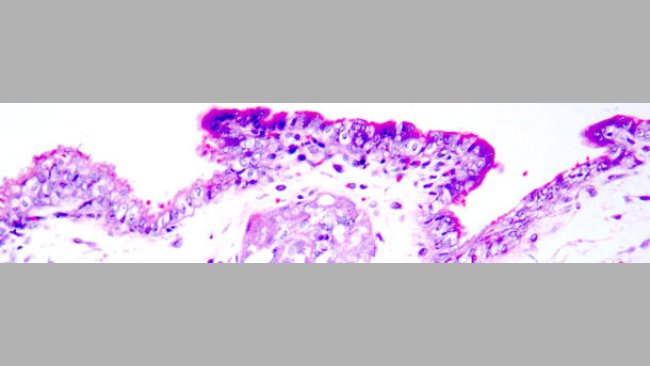

PCV2 vaccination of the gilts prior to insemination with PCV2 spiked-semen showed a clear decrease of viral load in the gilts as well as a much lower viral excretion that were compatible with foetus protection.